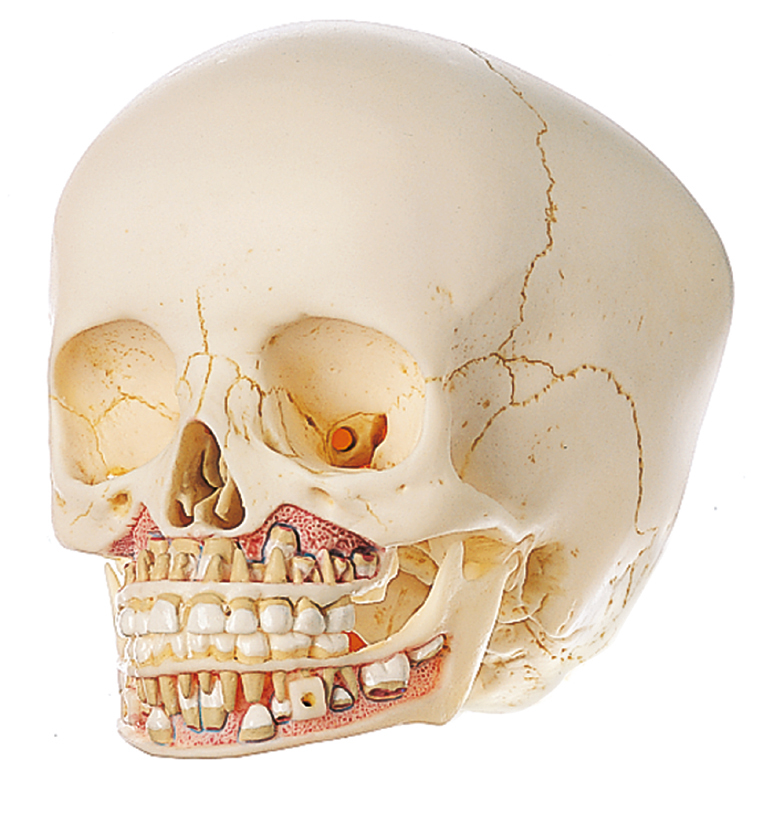

Анатомия детского черепа: Рентгеновские снимки и описание